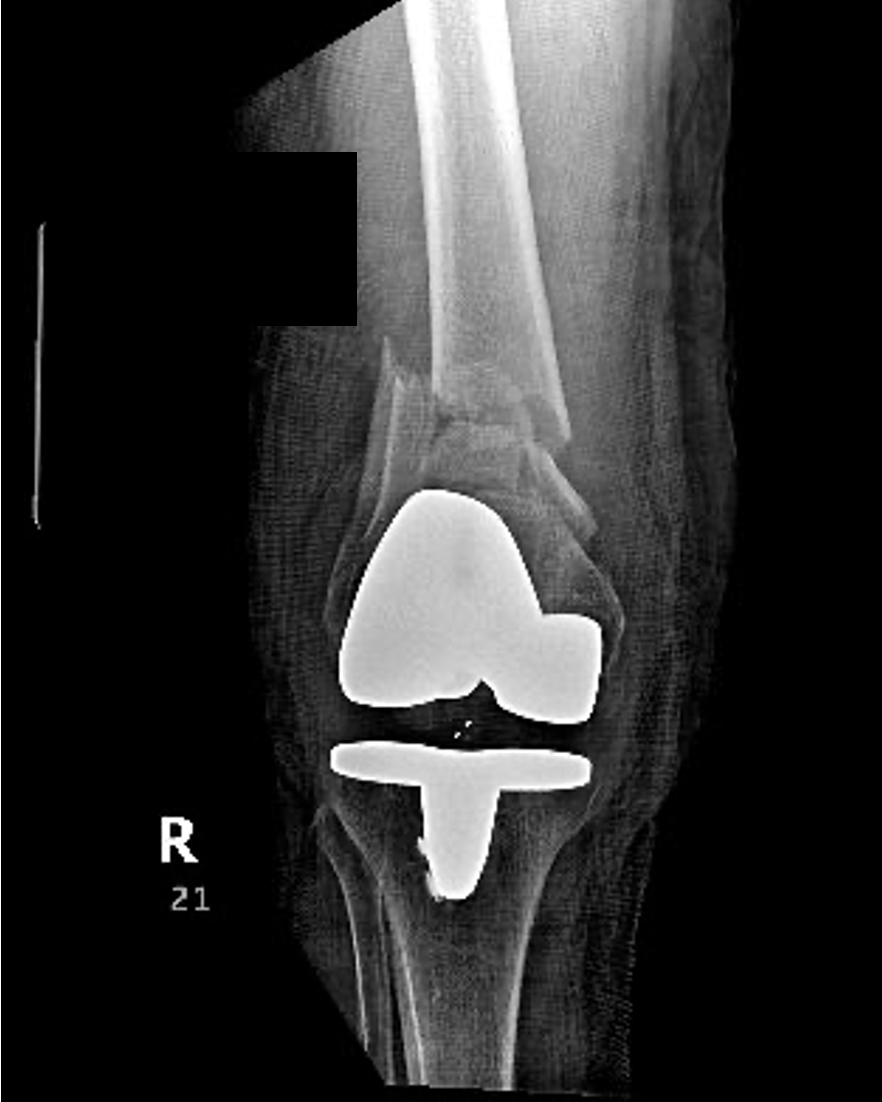

There were 37 33A, 2 33 B and 7 33C fractures. Forty-five percent (5/11) in the EWB group and fifty-one percent (18/35) in NWB group had periprosthetic fractures (P=0.73). (Table 2) Ninety-six percent (44/46 patients) were injured in low energy ground level falls. Two patients were high energy (falls > 4 feet) with one patient in each group (EWB and NWB).

Prior to definitive fixation, 2/46 (4.3%) were treated in an external fixator, 40/46 (87%) in knee immobilizer and 3/46 (6.5%) in a splint and 1 in traction. On average, surgery was performed 2.09 days from injury (SD1.86, range 0-11days). Ninety-one percent (42/46) were approached through a lateral incision. The remainder had surgical stabilization through an anterior approach (9%). The majority of patients (42) were treated with a pre-contoured locking plate with the distal construct locked. The use of locking and non-locking screws varied. However, the majority of patients (36) were treated with all non-locking screws above the fracture or a hybrid construct of one or two locking screws above the fracture. Ten patients were treated with 3 or more locking screws above the fracture. In three patients, there were additional plates used for fracture stabilization (2 NWB, 1 EWB).